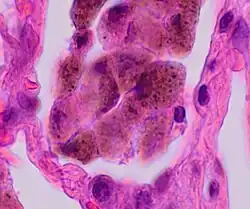

Comparison of pigmented pulmonary macrophages

| Disease | Macrophage name | Macrophage pigment appearance (HE stain) | Usual macrophage location | Associated medical history | Image | Image comment |

|---|---|---|---|---|---|---|

| Chronic pulmonary congestion | Siderophages | Brown-golden and refractile.[5] | Alveoli[6] |

|

Siderophage (black arrow), and interstitium with edema, hemosiderin deposition (black arrow) and collagenous thickening, indicating heart failure. |